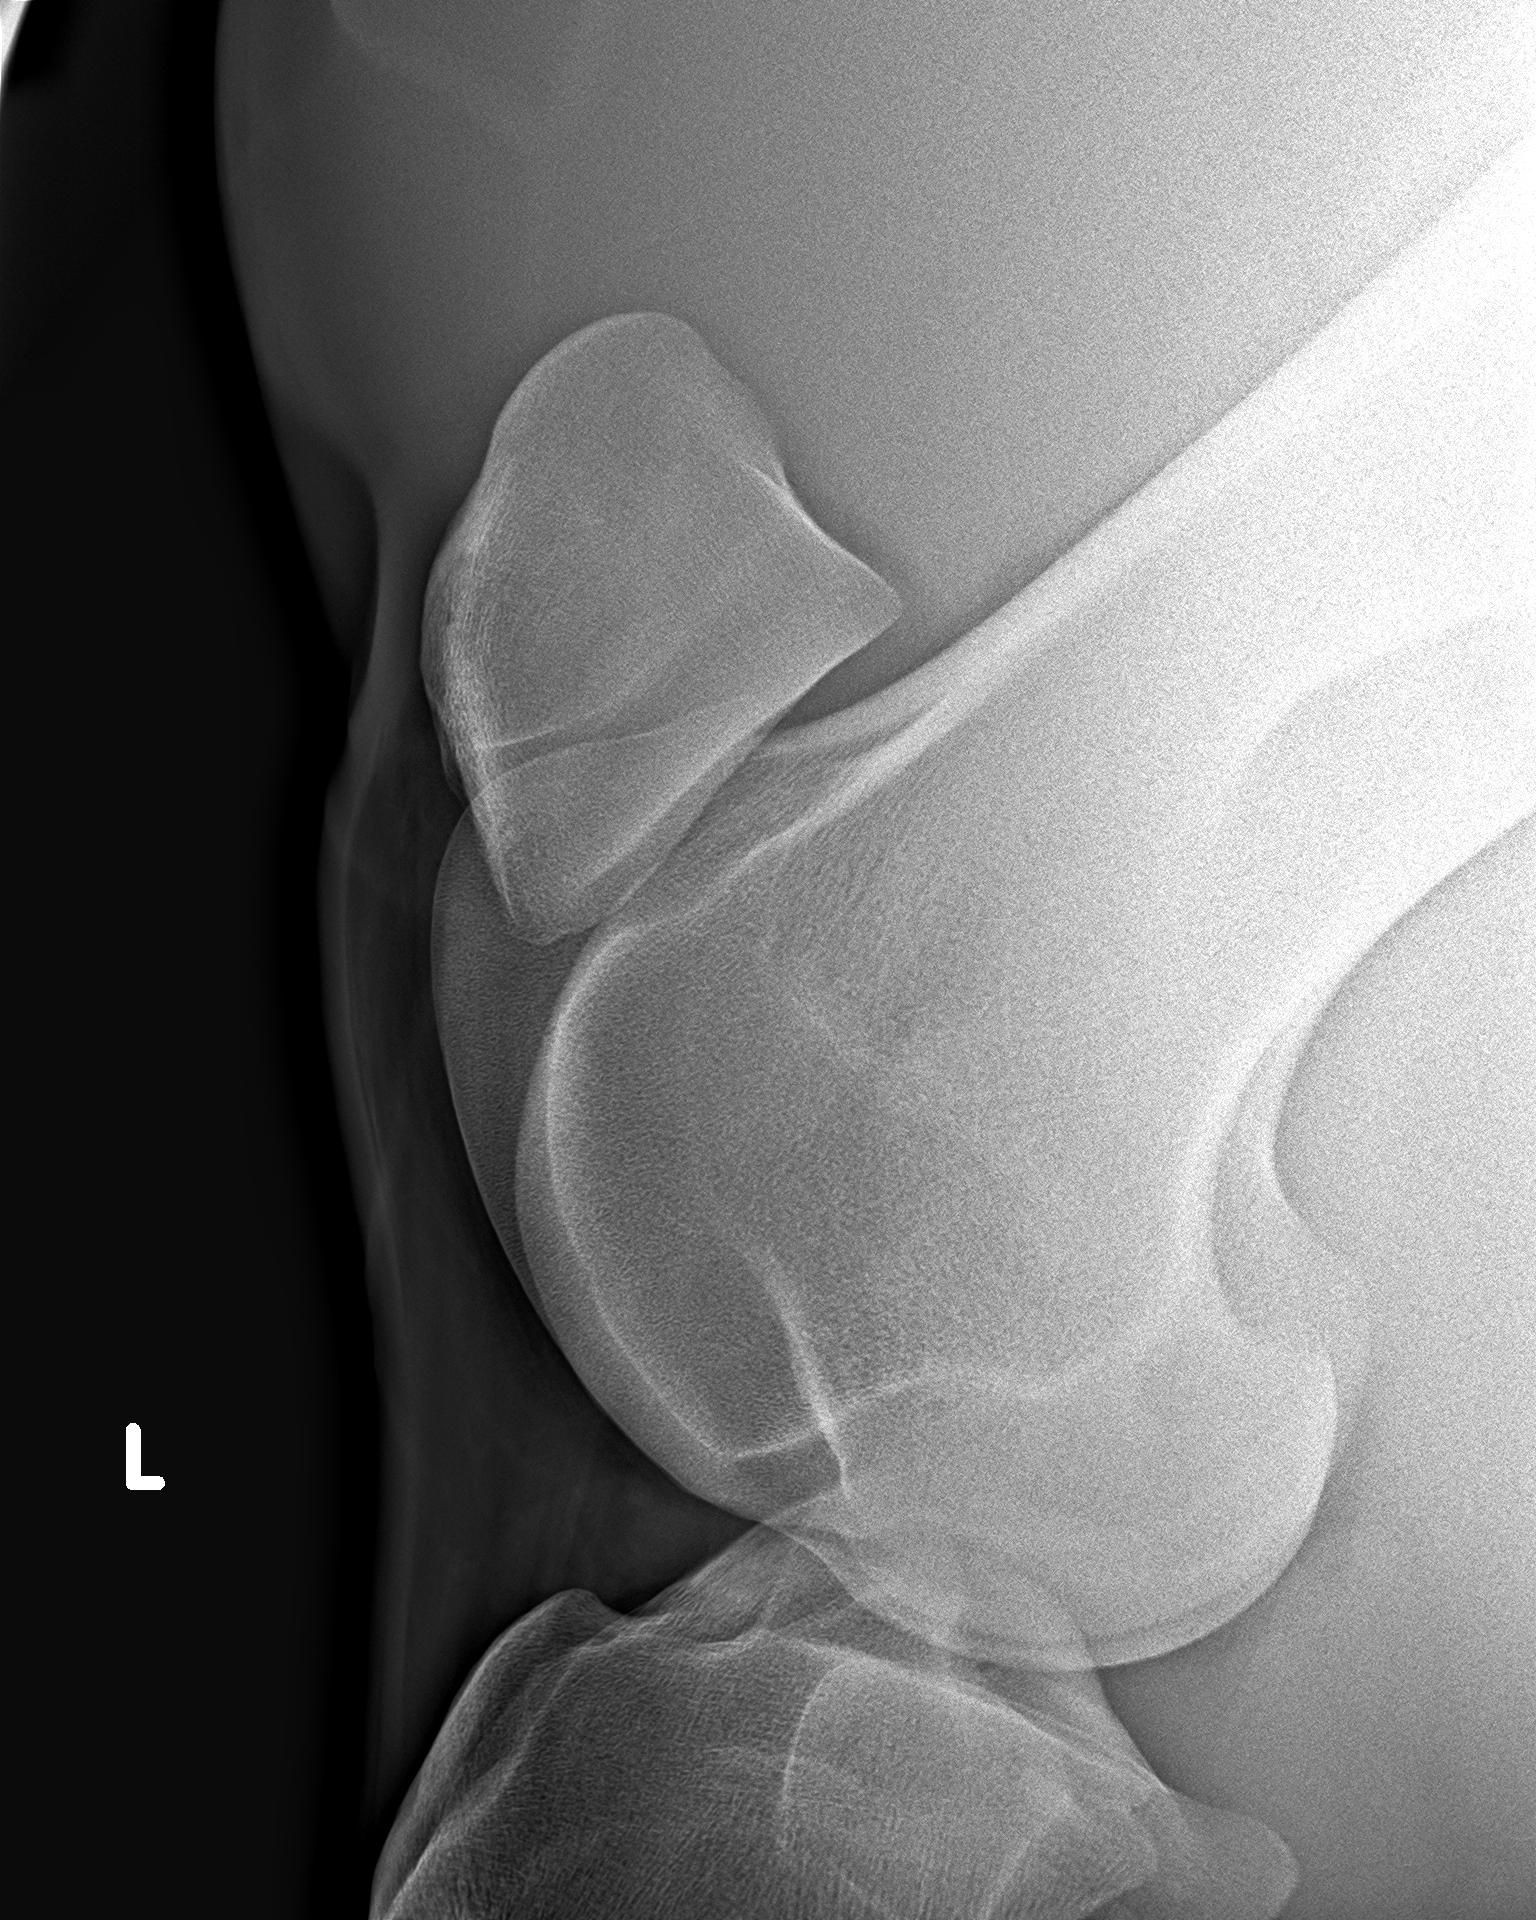

We utilize high-resolution Digital Radiography (DR) to deliver images with superior trabecular detail. Recognizing that every purchase has different requirements, we offer tiered radiographic protocols to suit the horse’s intended use and insurance tier.

Designed for general riding horses or to meet standard insurance requirements. This protocol covers the essential weight-bearing structures and common sites of concern. Views: Typically 36–40 images.

Coverage: Feet (Navicular/P3), Fetlocks, Hocks, and Stifles.

Option 2: The Performance / Extensive Set

Designed for high-performance Sport Horses, Hunters, and resale prospects. This comprehensive 60+ view series minimizes "grey areas" and provides a complete skeletal profile often required by US radiologist reviews. Views: 60+ images.

Extended Coverage: Includes all views from the Standard Set, plus:Axial Skeleton: Complete cervical spine (neck) and thoracolumbar (back) series to screen for impinging spinous processes ("Kissing Spines") or facet issues. Knees (Carpus): Full distinct views. Additional Angles: Skylines and obliques .